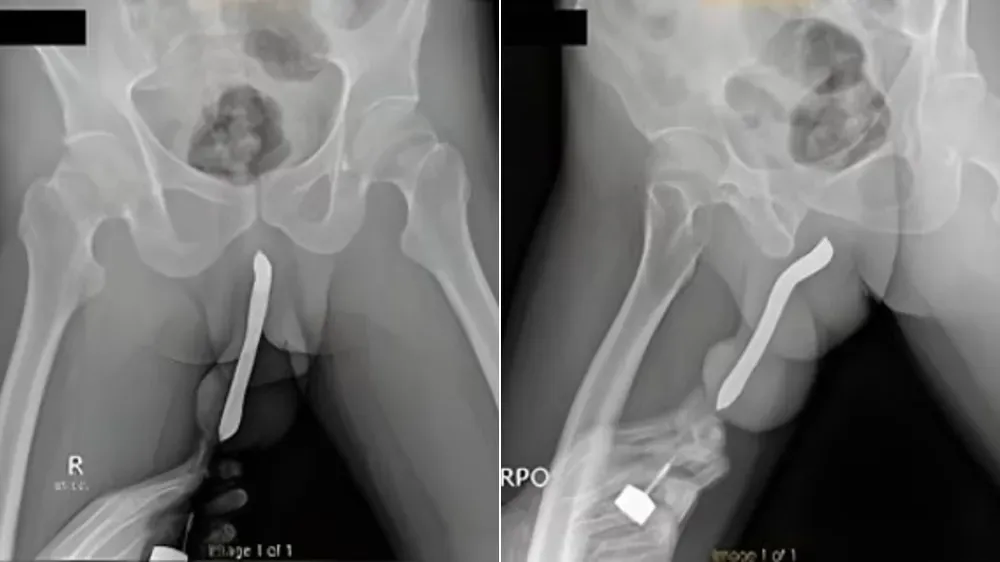

印尼男子為達到性高潮,竟拿牙刷塞進陰莖(圖/翻攝自《太陽報》)

對此醫生表示,當時男子陰莖彎曲腫脹像是根茄子,經X光檢測是陰莖骨折。

當地醫生表示,男子到院做檢查後,立即進行2小時的手術,所幸成功替男子取出牙刷並修復陰莖,而男子住院3天後離開,1個月後返回醫院復檢時,陰莖復原狀況良好,不僅能順利排尿,性功能也沒有受到任何影響。